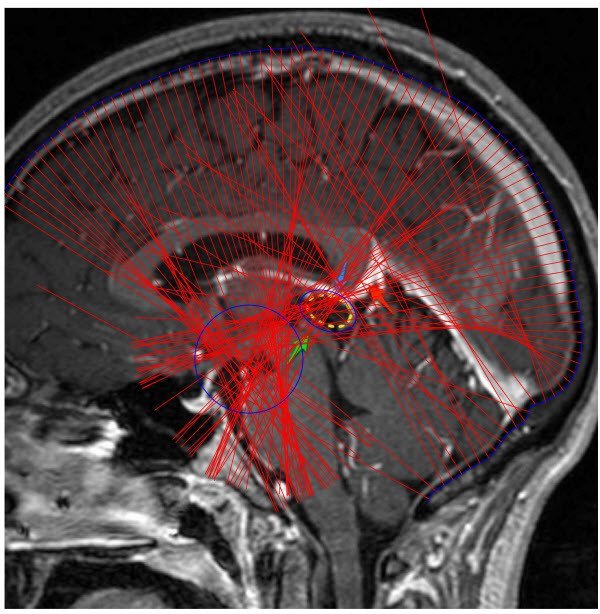

Внутренняя поверхность черепа человеческого тела показана на рисунках синей линией. Именно к данной линии были построены нормали, которые образуют характерные области пересечений.

Рис. 1. Пересечения нормалей внутренней поверхности черепа.

Очевидно, что на большинстве представленных рисунков (рис. 1-5, рис.7-8) область пересечения нормалей совпадает с областью расположения шишковидной железы (эпифиза). Этот факт даёт предпосылки для более углубленного изучения данного явления, учитывая особенности эпифиза и его важность.